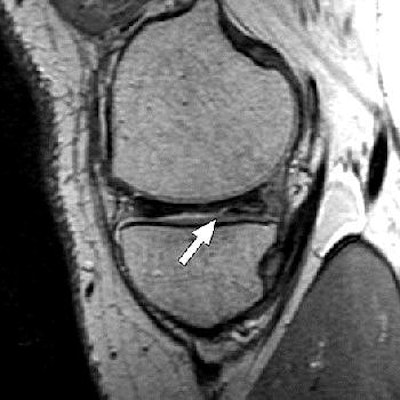

| Above, 27-year-old man with meniscal tear. Coronal 2D fast spin-echo (FSE) image (TR/TEeff, 4,000/38) shows tear (arrow). Middle, coronal 3D FSE extended echo-train acquisition (XETA) image (TR/TEeff, 2,500/38). Tear (arrow) was visible on two images of 2D FSE acquisition and 12 of coronal 3D FSE XETA images. Below, sagittal reformation of 3D FSE XETA dataset shows tear (arrow). |

Imaging at 3 tesla improved the resolution of 3D FSE XETA to 0.6-mm isotropic compared with 0.7-mm isotropic for 1.5-tesla images, the authors stated. In the volunteer with knee pain, 3D FSE XETA and 2D FSE revealed a meniscal tear in the posterior horn of the medial meniscus. Still, on the 3D FSE XETA, the tear was visible on a dozen images in the coronal plane versus two images from the 2D FSE acquisition.